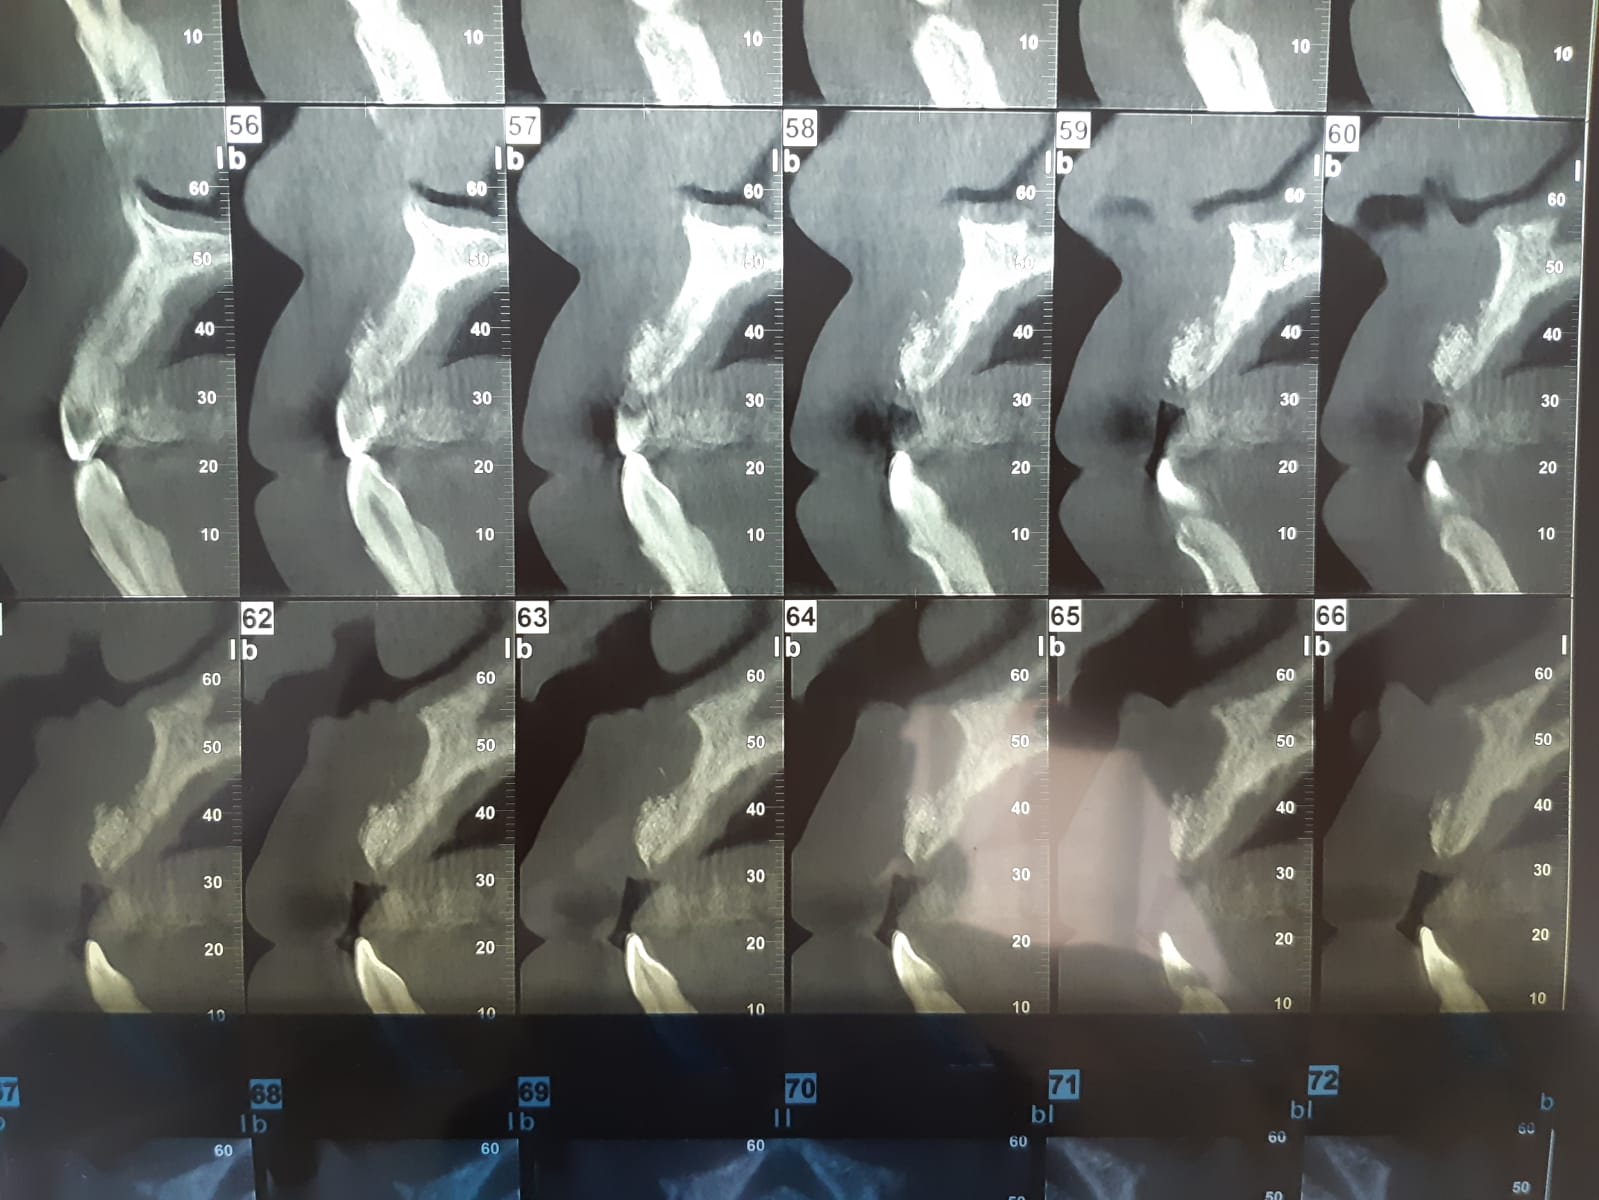

Voici un cas de grosse résorption antérieure que j'ai greffé Aout 2020

Le Scan de décembre soit 4 mois post Op montre un bon épaisissement du volume de crête par contre en Vestibulaire de 12 une coaptation pas très adhérente ...apparemment ..

Je dois poser 2 implants en 12 et 21 pour faire un bridge 3 eléments 12/21.

Faudra t il regreffer en vestibulaire ?..risque de spire apparente .(je dois poser 2 Implants de diamètre 3.75 par 13)

Et en plus présence du canal incisif palatin qui va être très proche de 21

C'est sur une hauteur de 8 mm env .Greffe au GTO ostéobiol

Je compte poser du 3.75 /13 . Possible que je rajoute du GTO en vestibulaire

4 mois post op, le neo-os n'est pas vraiment visible au cbct, la reussite d'une greffe d'apposition depend beaucoup de la bonne isolation du materiau, si c'etait le cas tu peux avoir une bonne surprise, surtout si tu attends 2 mois de plus.

En tout cas a ce stade, tu ne peux pas imaginer tricher avec de l'expansion, pas assez solide.

Le forage est aussi plus compliqué, car tu as des densites differentes qui vont deporter ton forage en vestibulaire. Ton guide ou ta main doivent rester fermes sur l'axe.